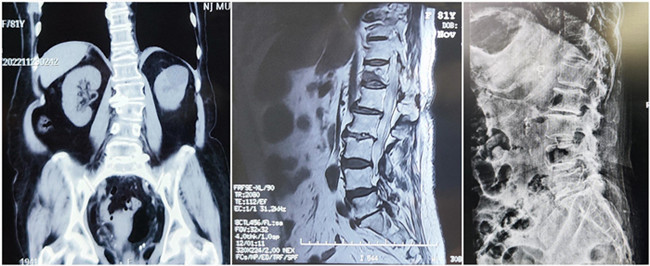

入院診斷:胸椎壓縮性骨折(T12)(主診斷);腰椎滑脫;腦梗死;高血壓1級;糖尿病。

*患者術(shù)前影像

王伯堯主任帶領(lǐng)其醫(yī)療團隊通過與患者的詳細溝通與交流,綜合評估椎體成形術(shù)治療超高齡椎體壓縮性骨折患者的安全性更高,以及病患病情的復(fù)雜性,最終決定運用智能化的手段,為患者制定個性化的手術(shù)方案,施行骨科機器人輔助下的T12經(jīng)皮椎體球囊擴張成形術(shù)。

? 手術(shù)效果確認

骨科機器人影像

*骨水泥置入效果良好